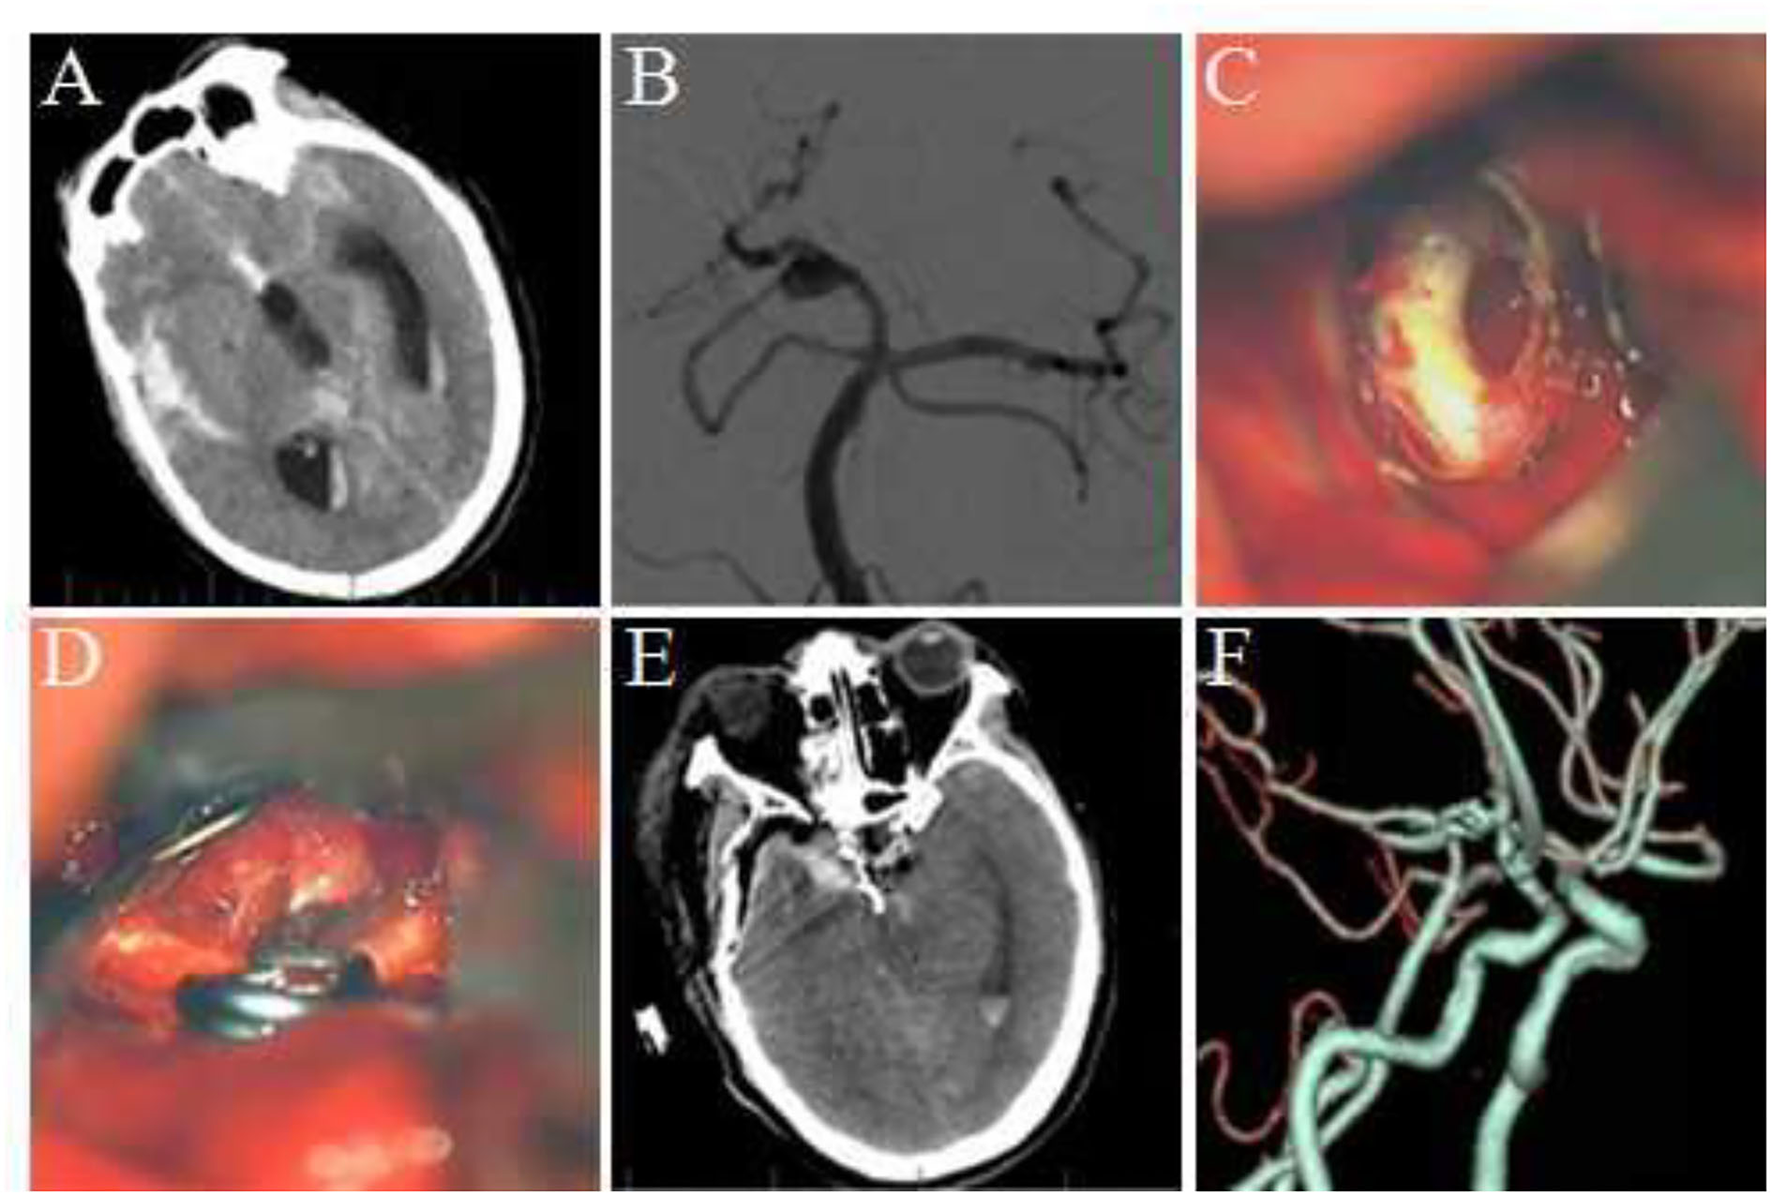

FIGURE 3

Figure 3. Clipping multiple aneurysms at the P1–P2 bifurcation of posterior cerebral aneurysm via the Dolenc approach. (A) Preoperative CTA revealed an aneurysm at the left posterior cerebral P1–P2 bifurcation with irregular shape and basilar artery and bilateral posterior cerebral artery stenosis. (B) DSA revealed two aneurysms at the bifurcation of P1–P2 of the posterior cerebral artery, exhibiting a lobulated shape. (C) During surgery, the P1–P2 bifurcation aneurysm could be seen in the lateral space of the internal carotid artery, which points to the posterior and medial side, and the oculomotor nerve and posterior communicating artery could be seen. (D) The optic nerve was pulled medially to increase the exposure range, and the P1 segment of the posterior cerebral artery, posterior communicating artery, and its perforating vessels could be seen. (E) Another aneurysm at the bifurcation of P1–P2 was exposed, pointing downward, and a part of the perforating vessels and oculomotor nerve from P2 could be seen. (F) Two aneurysm clips were used to clip the aneurysm. (G) A postoperative CT scan of the head. (H) The postoperative CTA revealed that the aneurysm was completely clipped with no residue and no vascular damage.